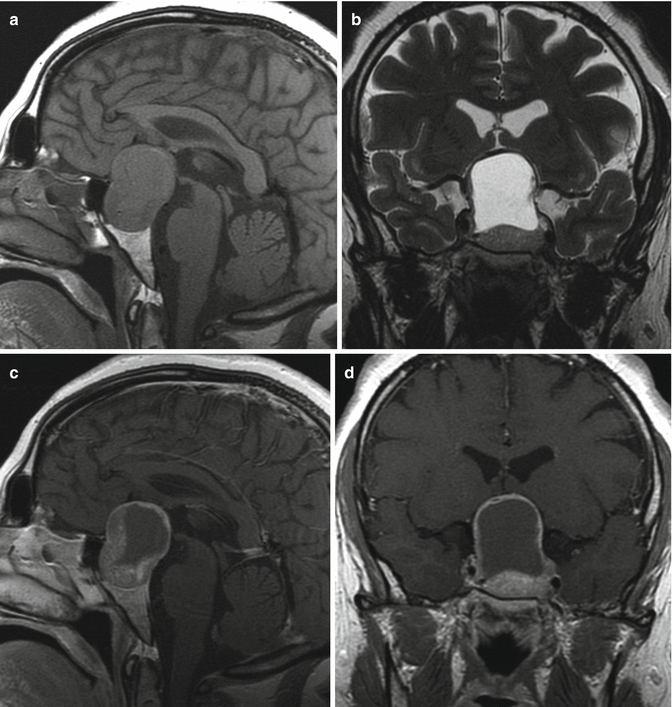

Caudothalamic Groove In The Coronal Plane . As the name suggests, it is located between the caudate.    — the first image is in the coronal plane depicting the foramen of monro and the third ventricle and the second.  grade 1 hemorrhage is limited to the region of the caudothalamic groove, usually less.    — germinal matrix hemorrhage (gmh) is also known as periventricular hemorrhage or preterm caudothalamic hemorrhage.  the junction of caudate and thalamus marks an important area, the caudothalamic. Sagittal planes are obtained through (1).    — sagittal planes:  the caudothalamic groove is an important landmark when performing neonatal cranial ultrasound.  parasagittal sonogram through lateral ventricles shows caudothalamic groove (arrow), separating caudate nucleus (c) from thalamus (t), and choroid plexus along posterior margin of thalamus (dotted line).  the space between the caudate head and thalamus is called the caudothalamic groove, which is an important structure to.